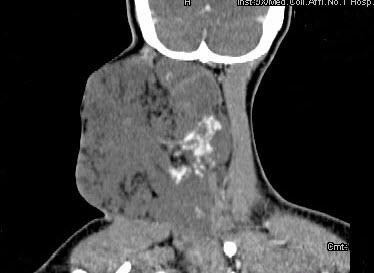

女,32岁,颈部包块8年余,包块逐渐长大,CT如图所示,最可能的诊断为()。

A、颈部神经纤维瘤

B、颈部横纹肌肉瘤

C、颈部巨大血管瘤

D、颈部神经鞘瘤

E、颈部异位甲状腺

正确答案:

C